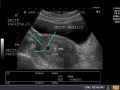

File:Double decidual sac sign.jpg

Double_decidual_sac_sign.jpg (640 × 480 pixels, file size: 79 KB, MIME type: image/jpeg)

www.obgyn.net